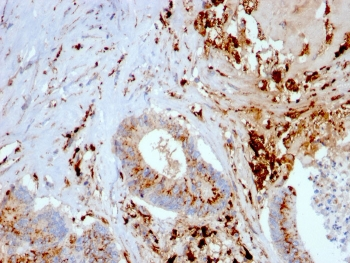

Cathepsin D Antibody

| Description | Cathepsin D Antibody |

| Tested applications | FC, ICC, IHC, IP, WB |

| Reactivity | Human, Mouse |